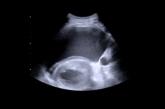

Article30-year-old woman • progressive dyspnea and peripheral edema • 35th week of gestation with a history of mild preeclampsia • Dx?Author:Anqi Abarbanell, PhDPublish date: July 21, 2023► Progressive dyspnea and peripheral edema► 35th week of gestation with a history of mild preeclampsiaRead More